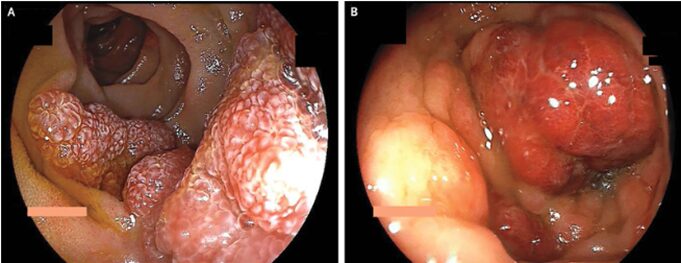

カポジ肉腫(HIVによく合併します)

54歳男性。特記すべき既往なし。 約10日間続く血清下痢と3ヵ月にわたる進行性の皮膚の発赤を主訴に救急外来受診した。 身体所見としては咽頭後壁に紅斑を伴う結節性…